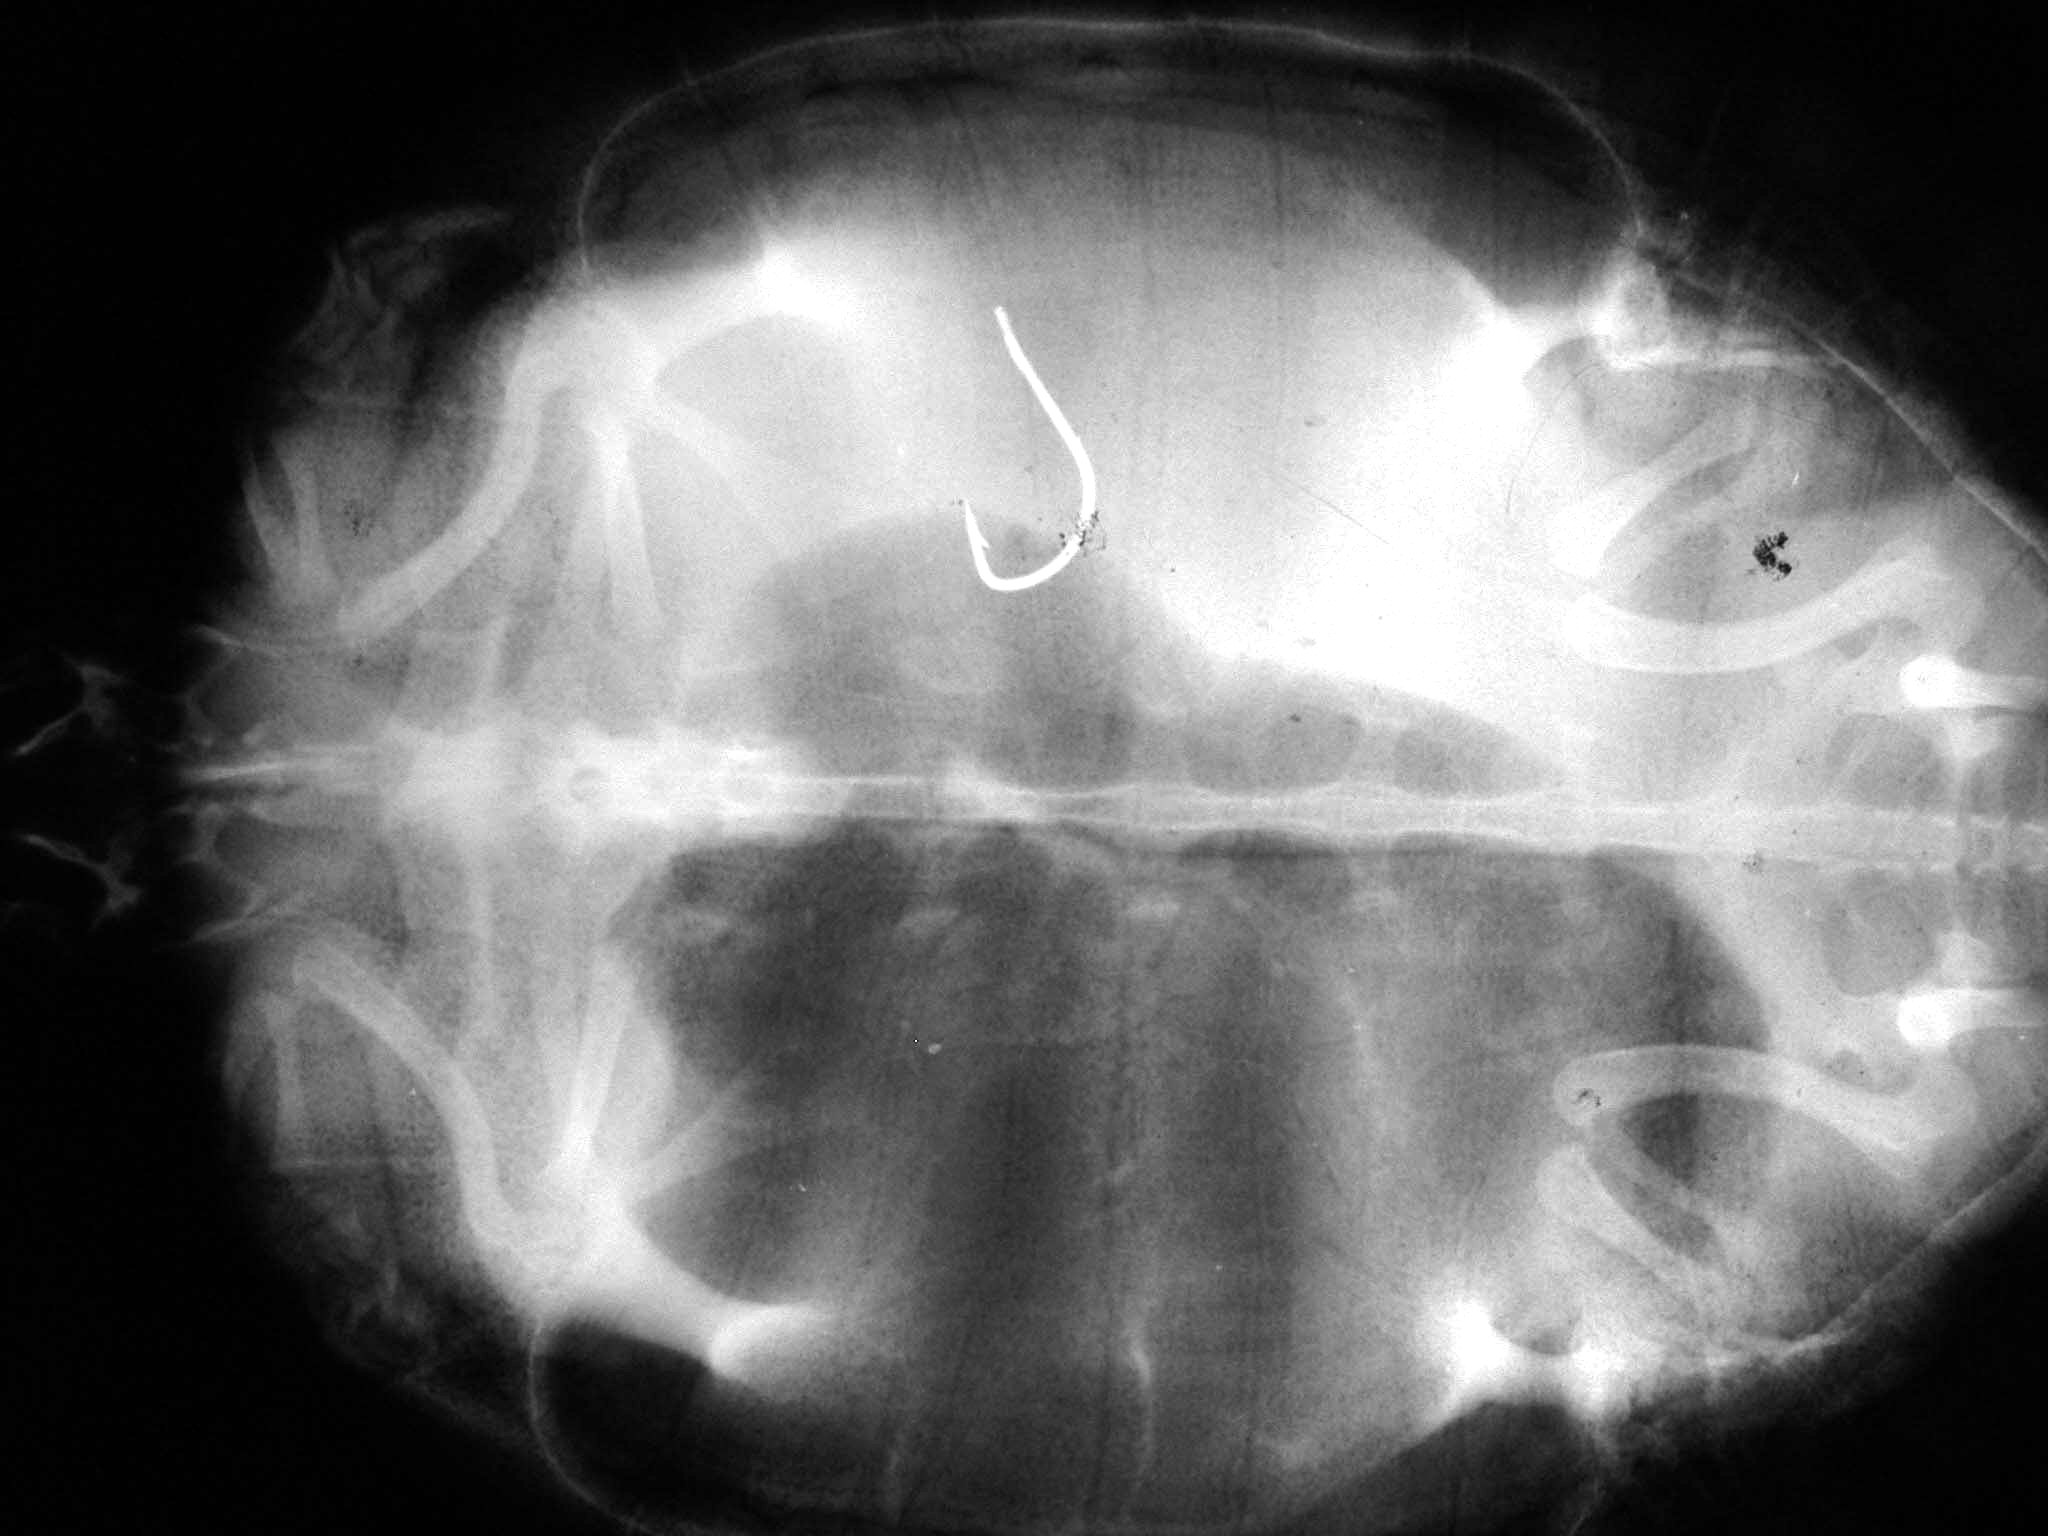

Angelhaken bei einer Rotwangenschildkröte aus dem Main